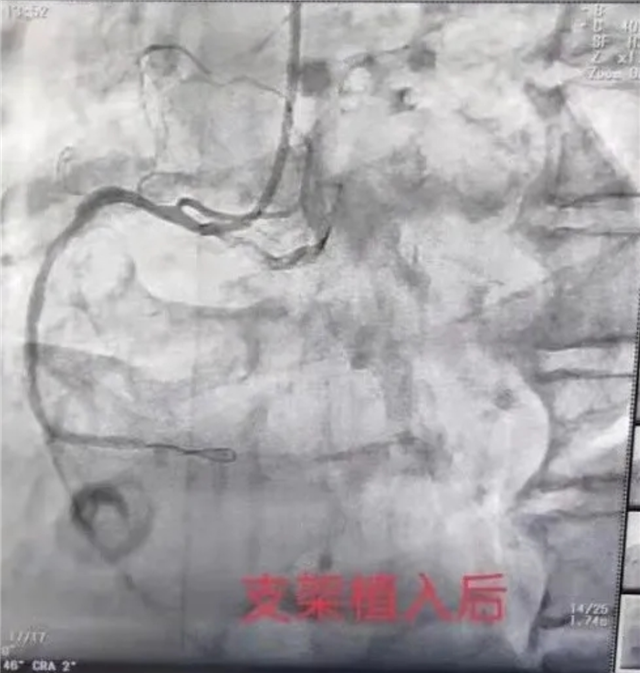

中国基层网商丘讯 在近一周内我院心内科接诊两例急性心梗病人,一位52岁男性,胸痛发作3小时后就诊,急诊送入我科后突发室颤,心肺复苏成功后,紧急给以急诊冠状动脉介入治疗(PCI)开通右冠状动脉;另一例为一位80岁老年男性,胸痛发作24小时就诊,入院后诊断为急性心梗,给以急诊冠状动脉介入治疗(PCI),术后血管开通良好。